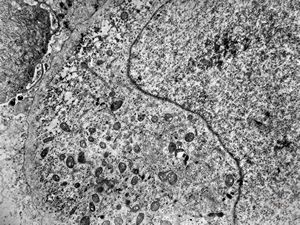

F,50y. | progressive multifocal leukoencephalopathy- viral particles in a glial cell